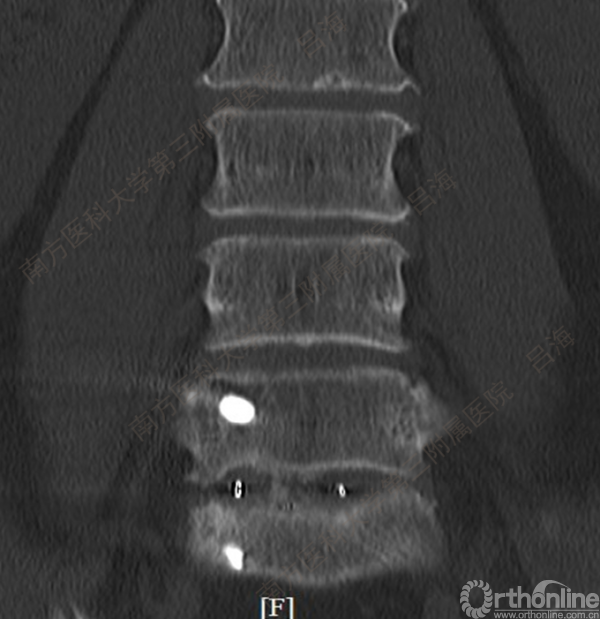

随着社会老龄化进程加快,胸腰椎退行性病变的治疗已经成为脊柱学术界的一个热点话题。MIS-TLIF手术可以治疗多种不同的胸腰椎退行性疾病,南方医科大学第三附属医院吕海教授结合病例为我们一一展示了该术式在治疗不同胸腰椎疾病时的具体手术过程。